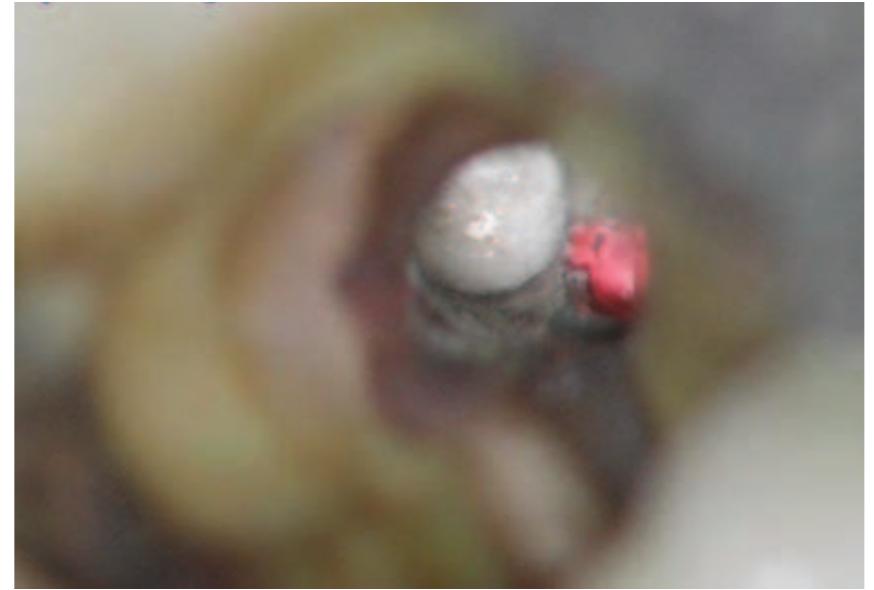

- This can then be placed into the root canal.